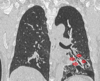

Q

A

Consolidación alveolar

How well did you know this?